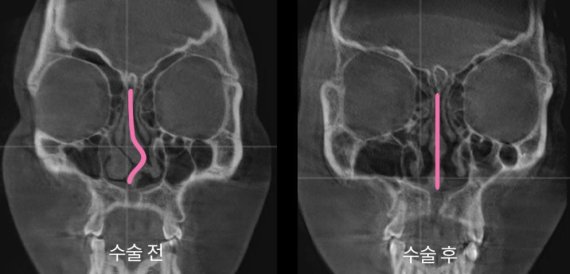

휘어있는 비중격과 수술 이후 곧아진 비중격 모습. 아이디병원 제공

코뼈골절은 모양 뿐만 아니라 코라인, 비중격 등 다양한 문제를 유발한다. 개인에 따라 증상도 달라 각 영역 전문의 간 협진 치료를 기본으로 한다.

코 외관(골절된 코뼈 교정)과 코 내관(휘어진 비중격 교정)을 각 전문의가 협진으로 수술하는 형태를 구축했다.